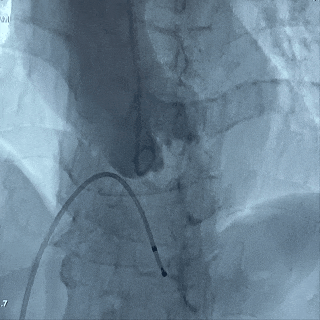

球囊扩张策略:20mm球囊预扩;

瓣膜选择:ScienCrown TAVTF25mm 0位定位释放;

20mm球囊扩张,轻微腰征无漏

25号瓣膜释放至全展开